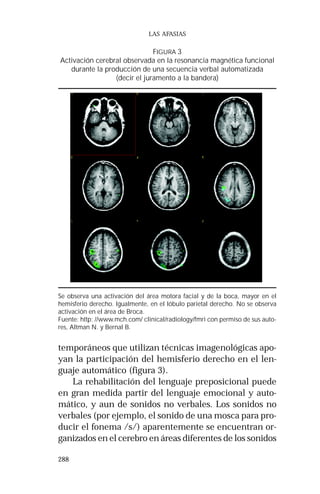

Durante los años noventa se fortalece la investiga-ción

funcional (FMRI) y la tomografía por emisión de

positrones (PET), que han permitido visualizar la acti-vidad

cerebral durante la realización de diferentes ta-reas

verbales (hablar, leer, pensar en palabras) (figuras

11 y 12). Además, surgió un nuevo modelo en la inter-pretación

de la organización cerebral de la cognición:

el modelo funcional, pues hasta este momento se había

utilizado un modelo lesional.

FIGURA 11

Resonancia magnética funcional (FMRI)

Fluidez verbal semántica

Encontrar palabras correspondientes a una categoría semántica. Se encuentra

activación de la región posteior del lóbulo temporal medio.

Fuente: www.mch.com/clinical/radiology/fmri con permiso de sus autores,

Altman N. y Bernal B.